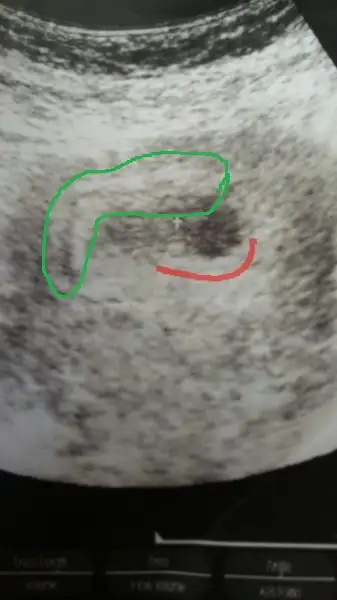

an bu sefer ki hamileliğinde bebek kesenin üst duvarındartı işareti olan yerde. baktıkça sanki palsenta yönü farklıymış geliyor. senin fotonu kullanarak çizdim . bir baksana plasentan yeşille işaretlediğim yer olabilir mi? (kırmızı çizgi sana ait canım. )

Evt olabilir cnm yukarıyı hic hesaplamadık:)diğer + isaretide benim çizdiğim kırmızı çizginin ucunda.dediğin gibi plasenta yukarda sanki.